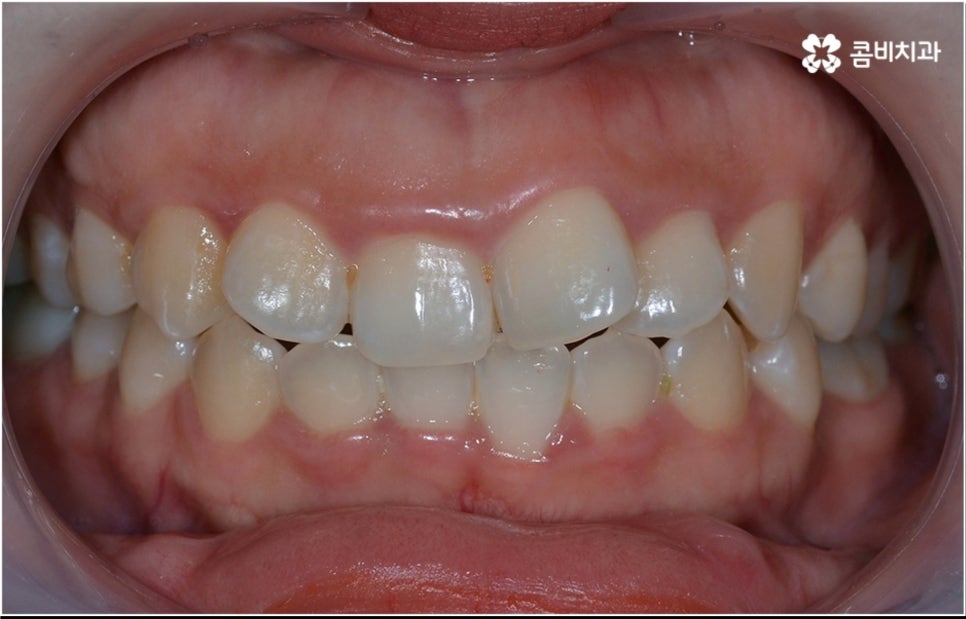

출처 아카이브 열기치열이 삐뚤어져서 불편함을 느끼고 교정 치료를 받고 싶어도 혹여 많이 비싸거나 기간이 너무 오래 걸리는 등 부담이 크지 않을까 염려가 되실 수 있습니다. 또한 중장년 성인분들의 경우 지금 나이에 교정 치료를 시작해도 되는지, 성인 치아교정 기간 은 얼마나 걸리는지 등도 많이 궁금해 하시고 있는데요.

결론부터 말씀드리자면 교정 치료에 적기가 따로 정해져 있는 것은 아니며 성인 치아교정 기간 의 경우 환자분들의 상황에 따라 달라지기 때문에 먼저 정밀 검진을 받아보신 후 숙련된 의료진과 상담을 하시면서 자세히 알아보시는 것을 권유드리고 있어요.

치열이 삐뚤어져 있으면 기능적 심미적으로도 불편하지만 구강 건강과 관련하여 음식물 찌꺼기가 자주 끼고 충치 및 잇몸병과 같은 구강 질환에 노출될 가능성이 높아지는 등 관리가 어렵다는 문제도 커지기 때문에, 점점 길어지는 노년기에 건강하고 활기찬 생활을 하기 위해서 구강 건강이 굉장히 중요한 역할을 한다는 점을 상기해 봤을 때 중장년 성인 교정 치료에 대해서 괜한 두려움으로 미루기 보다는 더 늦기 전에 검진을 받아보고 필요한 도움을 받을 수 있는지 적극적으로 알아보는 것이 보다 바람직한 태도라고 할 수 있을 거예요.